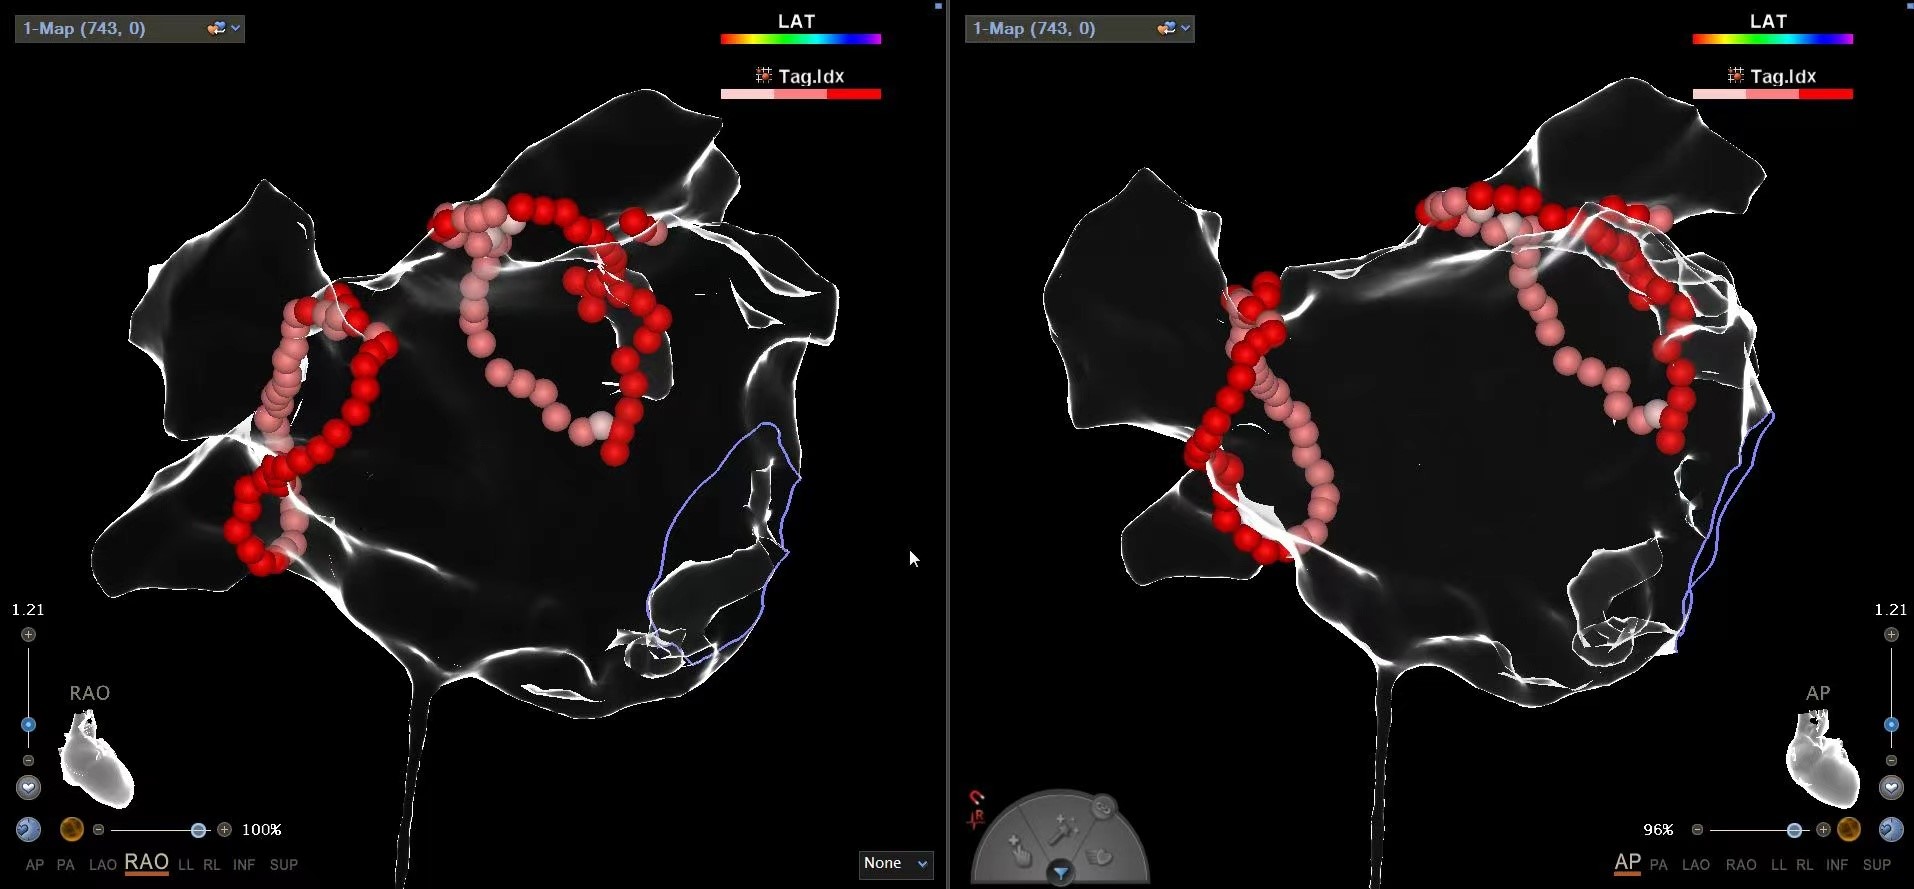

陈弹主任介绍,射频消融术是一种局部麻醉下进行的微创手术,不需要开胸和全身麻醉,患者在手术过程中全程清醒,随时可将自己的感受告诉医生,避免了全麻的副作用和手术风险;同时,手术创口只有一个针孔大小,术后第二天就可以下床活动。相较于传统的药物治疗,射频消融术在三维技术标测下对肺静脉前庭进行完全电隔离,可有效治疗心房颤动,减少并发症发生。射频消融术由于其可靠的安全性,适用于绝大多数房颤患者,目前已成为房颤根治的治疗手段。